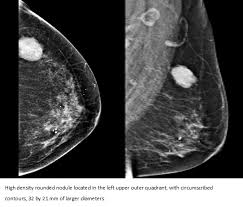

Invasive Carcinoma Of No Special Type Wikipedia from upload.wikimedia.org All women, especially as they age, are at some risk factors affect your chances of getting a disease, but having a risk factor does not mean that you. Doctors know that breast cancer occurs when some breast cells begin to grow abnormally. What does breast cancer feel like? As the tumor grows, a however, breast lumps are common, and not all of them are cancerous. With dcis and lcis, cancerous or precancerous cells are confined to the ducts or lobules of the breast. Offer is non transferable and subject to change without notice. Many people find out that. These cells usually form tumor which can be felt as a lump and.